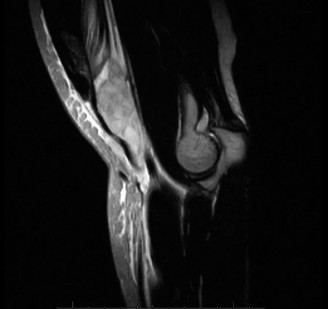

The correct answer is (E). This patient has a suspected distal biceps tendon rupture. He has the classic presentation of an eccentric overload injury along with a pop and pain in the antecubital fossa. However, his examination is inconclusive for complete versus partial tendon tear. The hook test is performed by asking the patient to actively flex the elbow to 90 degrees and fully supinating the forearm (see Fig. 2–119). The examiner then attempts to hook their index finger under the lateral edge of the tendon and palpate a cordlike structure representing the biceps tendon. This test has been shown to be both highly sensitive and specific (up to 100%), but it is inconclusive in this case. An MRI is warranted to assess the integrity of the distal biceps tendon, to distinguish between complete versus partial rupture (Fig. 2–120). This could alter management as the optimal treatment of partial tendon ruptures is not entirely clear. There is relative urgency to doing this, as early surgical intervention after injury is preferred to facilitate primary repair.

Figure 2–120 MRI depicting distal biceps tendon rupture.